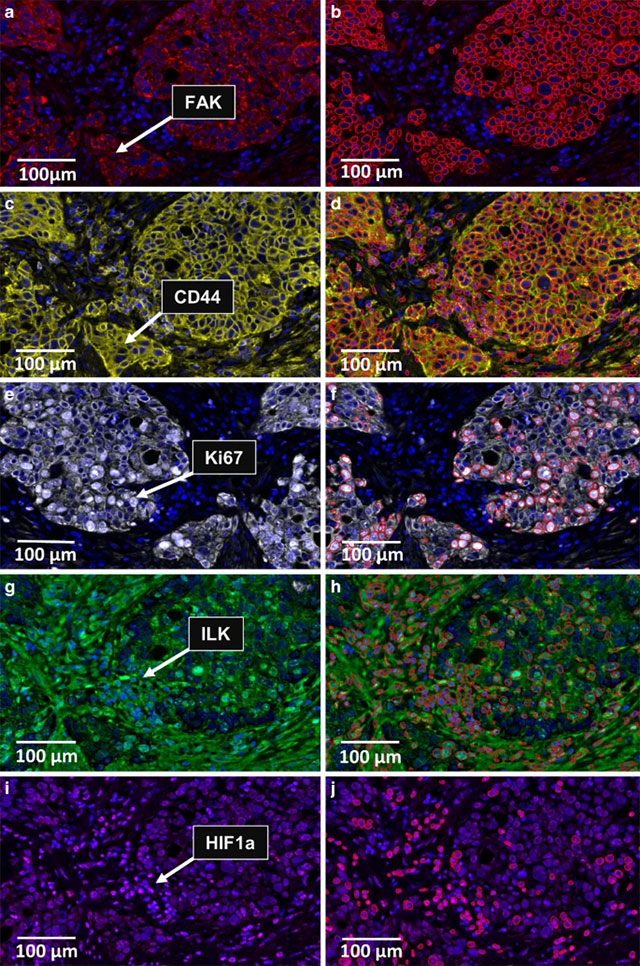

Credit: Igbo et al., 2024

The technique of “immunofluorescence” was born decades later at Harvard Medical School in 1941, when Albert Coons modified the xanthene-based fluorophore fluorescein so that it could be linked to an antibody, then used the conjugate to label bacterial polysaccharide on pneumococci in mice.

Now immunofluorescence is an indispensable technique for locating proteins and other molecules within cells. Here, a many-color “multiplex” format distinguishes several cell types in the tumor microenvironment of esophageal cancer.